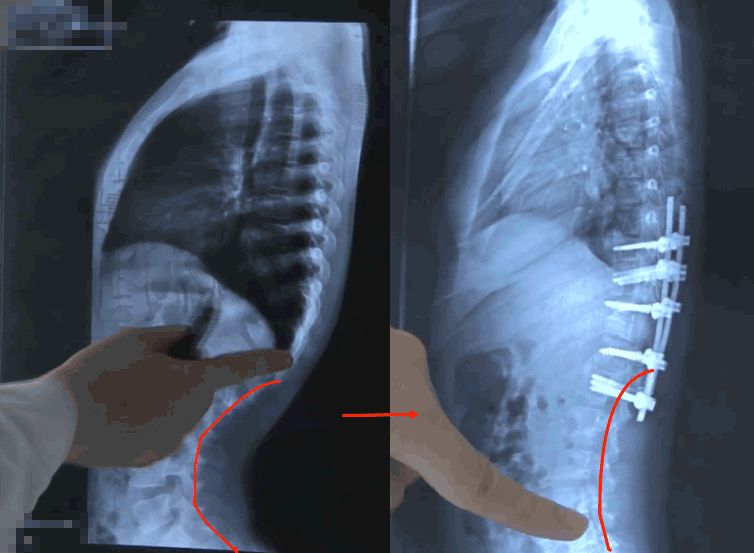

歷時五個小時,手術終于順利完成了,看著狀況平穩的塔吉,伊力一顆懸著的心也放下了。

矯正前(左)矯正后(右)